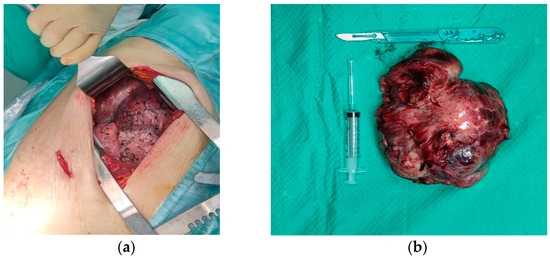

A Case Report of Doege–Potter Syndrome: A Rare Cause of Hypoglycemia in a Patient without Diabetes

Hypoglycemia in patients without diabetes is a diagnostic challenge for the endocrinologist. Sometimes it is related to rare causes such as Doege–Potter Syndrome (DPS). DPS is caused by an abnormal insulin-like grow factor 2(IGF-2) that retains part of the E domain during the [...] Read more.

Hypoglycemia in patients without diabetes is a diagnostic challenge for the endocrinologist. Sometimes it is related to rare causes such as Doege–Potter Syndrome (DPS). DPS is caused by an abnormal insulin-like grow factor 2(IGF-2) that retains part of the E domain during the production process, resulting in a longer peptide called “big-IGF-2”. We present a case report of DPS with emphasis on the diagnosis and especially on the difficulties in interpreting the biochemical findings. An elderly patient with an intrathoracic neoplasm and hypoglycemia underwent various tests: insulin autoantibodies and fasting test were both negative. She had low values of IGF-1 and normal values of IGF-2 that apparently excludes a diagnosis of DPS. The evaluation of the IGF-2/IGF-1 ratio is the most important test because a ratio >10 is widely considered to be indicative of non-islet cell tumor hypoglycemia (NICTH). Glucose infusion and steroid therapy were used to control the hypoglycemia, but the definitive treatment was surgery, which almost immediately reversed the hypoglycemia. The differential diagnosis of hypoglycemia should include rare causes such as DPS, and the IGF-2/IGF-1 ratio is a useful tool. Full article

Figure 1